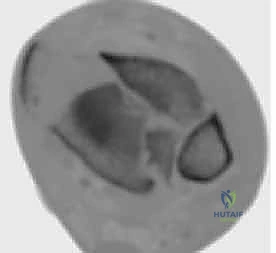

2. التصوير المقطعي المحوسب (CT Scan) - المعيار الذهبي

لا يمكن إجراء جراحة حديثة لكسر البيلون دون إجراء أشعة مقطعية. لماذا؟

كشفت الأبحاث المتقدمة (مثل أبحاث كول Cole وزملائه) والتي يعتمد عليها الدكتور هطيف، أن الأشعة المقطعية، وخاصة مع إعادة البناء ثلاثي الأبعاد (3D Reconstruction)، تسمح برسم خريطة دقيقة لكل قطعة عظمية مفتتة في السطح المفصلي (AO/OTA 43-C3).

تظهر الأشعة المقطعية النمط الثابت لتفتت البيلون والذي يتكون عادة من ثلاث قطع رئيسية:

* القطعة الأمامية الجانبية (Chaput fragment): متصلة بالرباط الظنبوبي الشظوي الأمامي.

* القطعة الخلفية (Volkmann fragment): متصلة بالرباط الظنبوبي الشظوي الخلفي.

* القطعة الأنسية (Medial Malleolus): متصلة بالرباط الدالي.

وفي الوسط، توجد منطقة "الانهيار المفصلي" (Die-punch fragment) التي تُدفع داخل العظم.